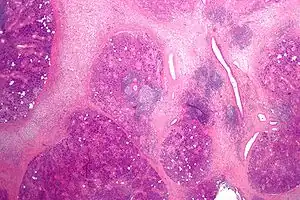

Microanatomy

The gland is internally divided into lobules. Blood vessels and nerves enter the glands at the hilum and gradually branch out into the lobules.

Acini

Secretory cells are found in a group, or acinus. Each acinus is located at the terminal part of the gland connected to the ductal system, with many acini within each lobule of the gland. Each acinus consists of a single layer of cuboidal epithelial cells surrounding a lumen, a central opening where the saliva is deposited after being produced by the secretory cells. The three forms of acini are classified in terms of the type of epithelial cell present and the secretory product being produced - serous, mucoserous, and mucous.[17][18]

Ducts

In the duct system, the lumina are formed by intercalated ducts, which in turn join to form striated ducts. These drain into ducts situated between the lobes of the gland (called interlobular ducts or secretory ducts). These are found on most major and minor glands (exception may be the sublingual gland).[17]